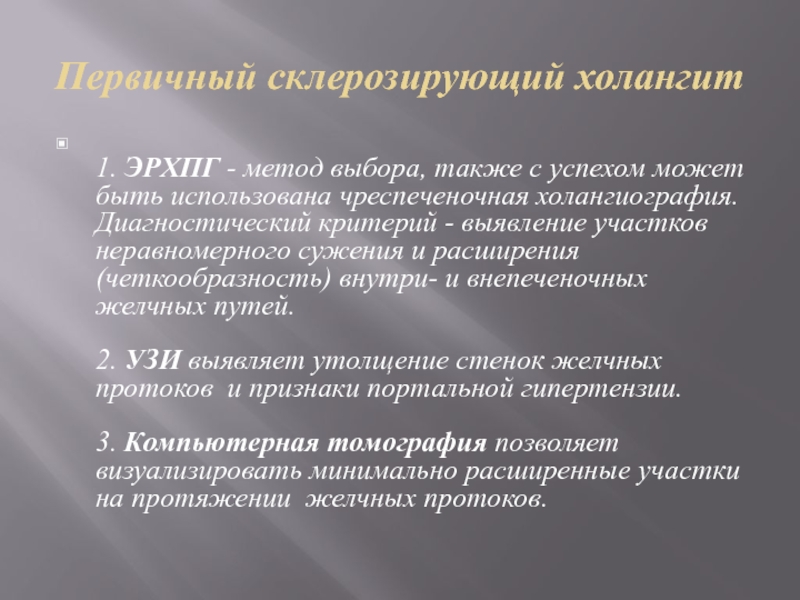

Фотографии и изображения, связанные с симптомами первичного склерозирующего холангита

Раздел: Кладезь мудрости